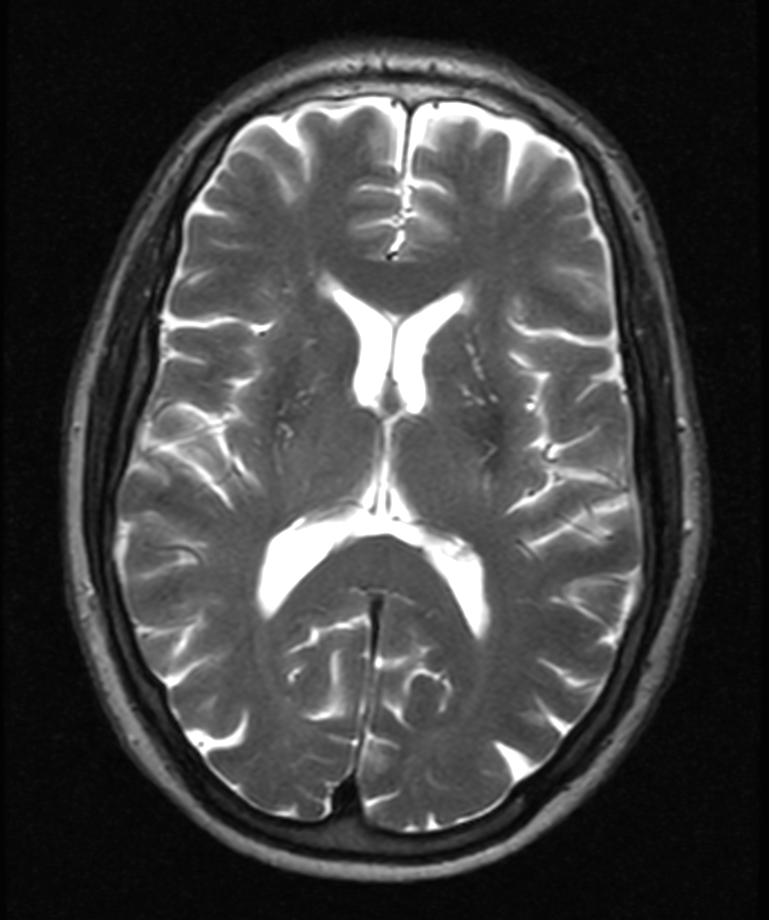

Axial T2w TSE

23Na bFFE (axial reformat)